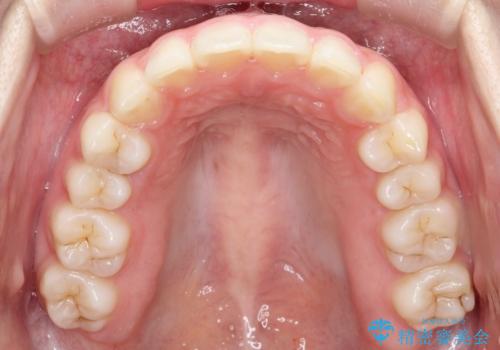

- 前歯の隙間と、出っ歯に見えることを主訴に来院されました。

できるだけ目立たない装置をご希望されましたので、インビザラインにて治療を行いました。

治療中は、できるだけ前歯を下げることができるように”顎間ゴム”を使用します。

”顎間ゴム”を利用することで、奥歯を後ろに動かす力を強めることができます。